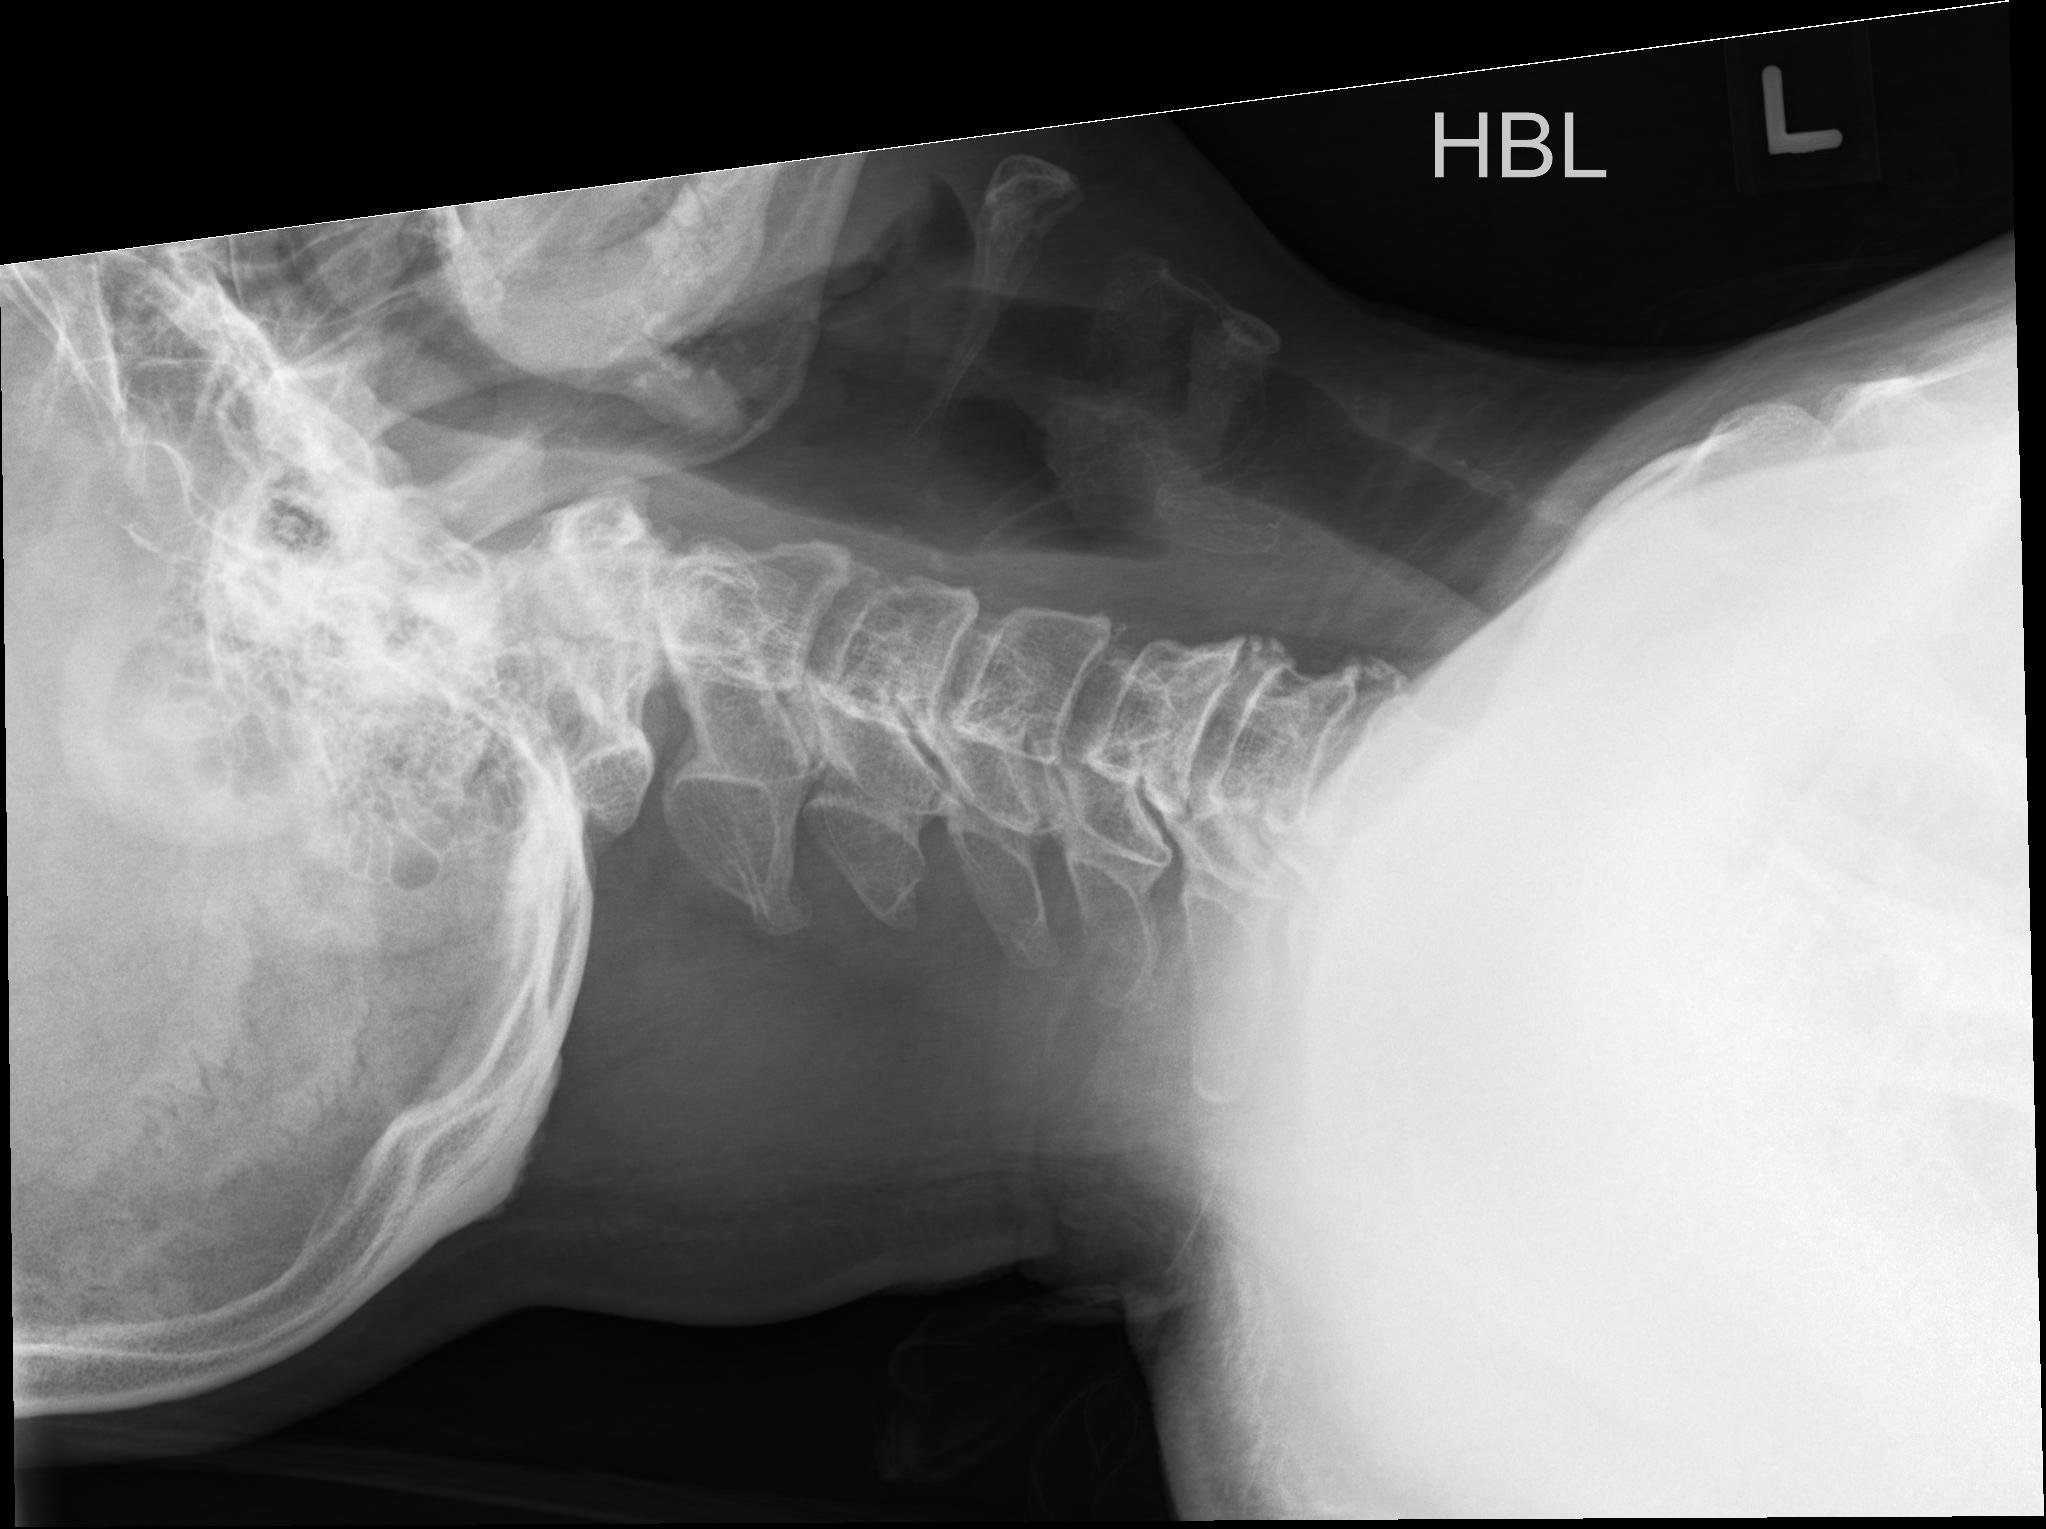

| Study | ID | Date | Accession # | Thumbnails | Report | XR ELBOW, AP & LAT, LEFT | 2766356 | 08/21/2019 | 2766356 | ... | MR WHOLE SPINE (FULL STUDY) | 32376 | 08/23/2019 | 2766095 | ... | XR CERVICAL SPINE, AP & LATERAL | 2765876 | 08/20/2019 | 2765876 |